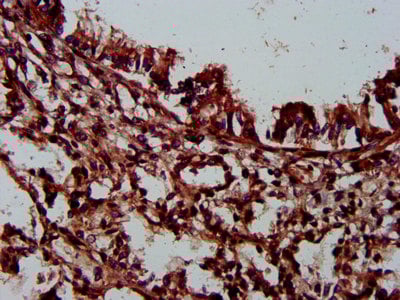

IHC (Immunohiostchemistry)

(IHC image of AAA234632 diluted at 1:300 and staining in paraffin-embedded human lung tissue performed on a Leica BondTM system. After dewaxing and hydration, antigen retrieval was mediated by high pressure in a citrate buffer (pH 6.0). Section was blocked with 10% normal goat serum 30min at RT. Then primary antibody (1% BSA) was incubated at 4 degree C overnight. The primary is detected by a biotinylated secondary antibody and visualized using an HRP conjugated SP system.)